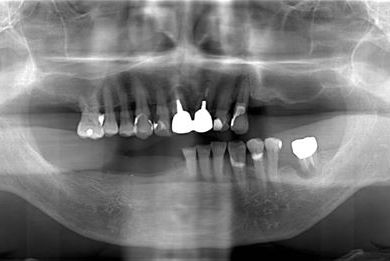

骨再生スピードインプラント治療+遊離歯肉移植

| 性別/年齢 | 男性 / 66歳 | ||||||||||||||||||||||||||||||||

| 治療方針 | サイナスリフトにより上顎洞を拳上し、インプラント治療を可能にする。 | ||||||||||||||||||||||||||||||||

| 治療内容 | インプラント8本(サイナスリフト、抜歯即日スピードインプラント)、ハイブリッドセラミッククラウン9本、遊離歯肉移植 | ||||||||||||||||||||||||||||||||